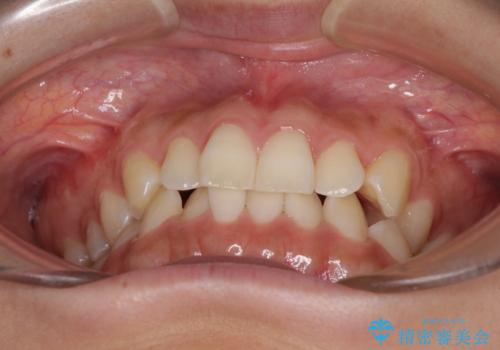

- 前歯の叢生と、奥歯の咬み合わせの悪さを気にして来院された患者様です。

左下には後続永久歯の欠損した乳歯が残存しており、叢生を相まって咬合関係が乱れていました。

乳歯は抜歯し、インビザラインにて矯正治療を行いながら、並行してインプラントによる補綴治療を行うこととしました。